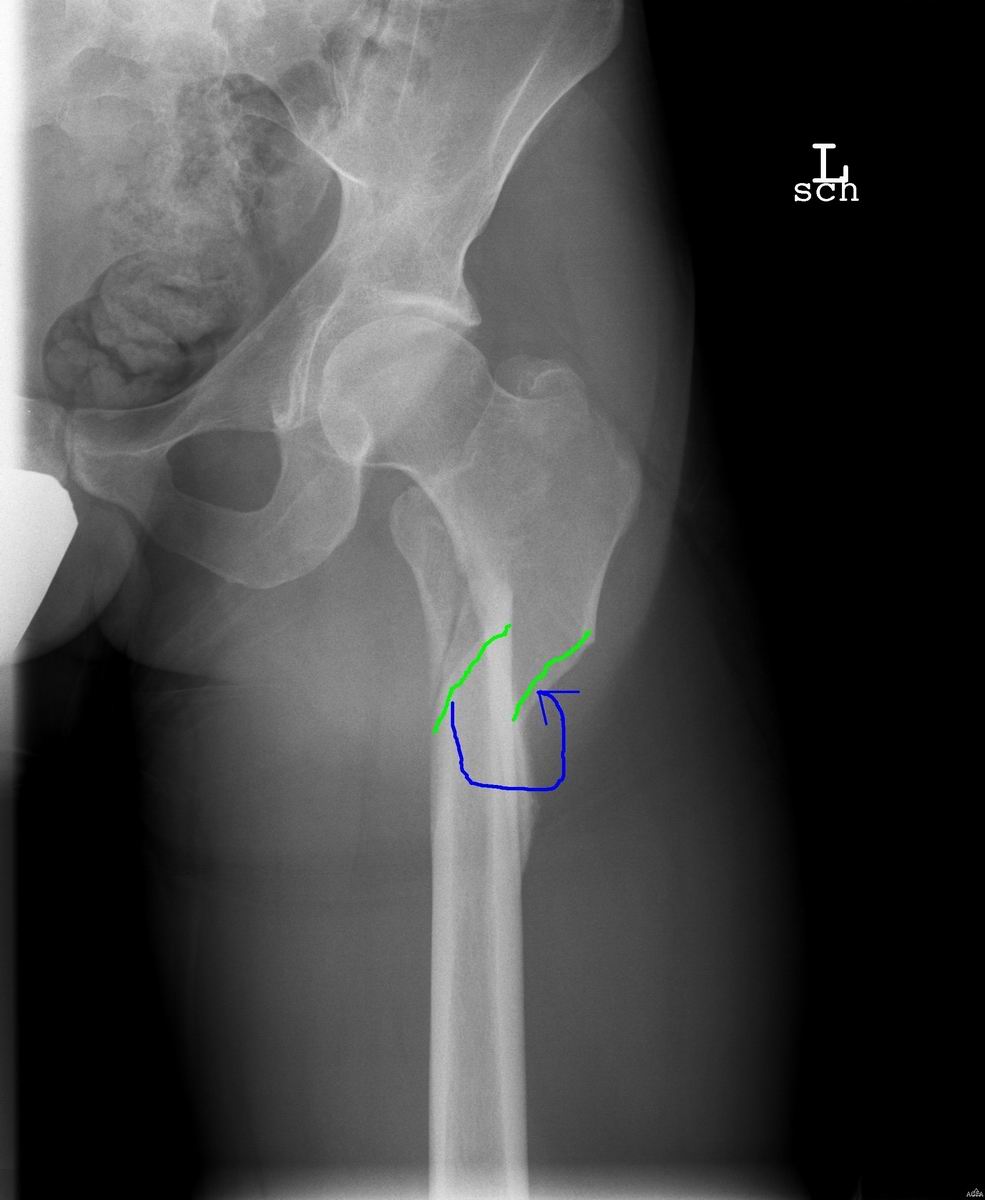

Heute habe ich von der Žrztin die CD mit nicht weniger als 19, davon 13 Röntgen-, Bildern meines linken Beines von der Žrztin zurück erhalten. Wenn ich dazu die zahlreichen Beschüsse meiner linken Hand mit Röntgenstrahlung aus der Vergangenheit bedenke, könnte ich ja direkt mal über einen halbwegs passenden Wechsel meines Avatars nachdenken

Da ich den Röntgenbild-Thread nicht mehr finde, an dieser Stelle eine kleine Auswahl.